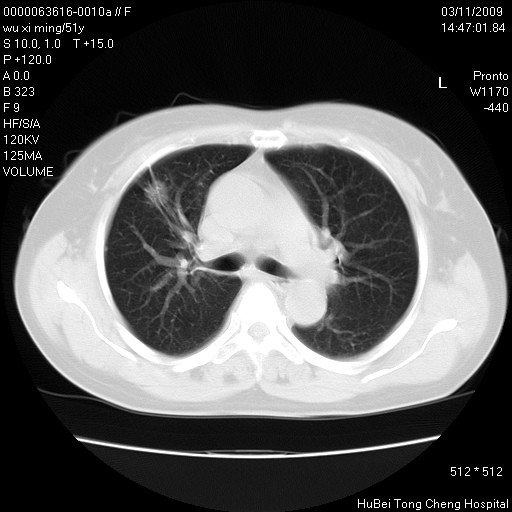

患者 女,51岁。因“胆囊炎,胆囊结石”,行常规术前胸部x线检查发现:右上肺结节病灶,建议行进一步检查。患者无咳嗽、咳痰及咯血等呼吸道症状,近期出现背部疼痛不适。

胸部ct轴位平扫(层厚10mm,螺距1.5,重建间隔10mm;部分层面:层厚3mm,螺距1.0,重建间隔3mm),图像如下:

1、周围型肺癌。(毛刺正、血管束集征,分叶。)

集束征,胸膜牽拉征,毛刺,淺分葉高度提示ca.